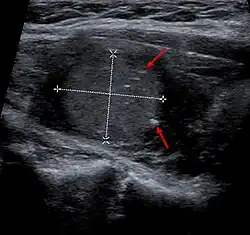

| Micrograph of medullary thyroid carcinoma with amyloid deposition (left of image). Near normal thyroid follicles are also seen (right of image). H&E stain. | |